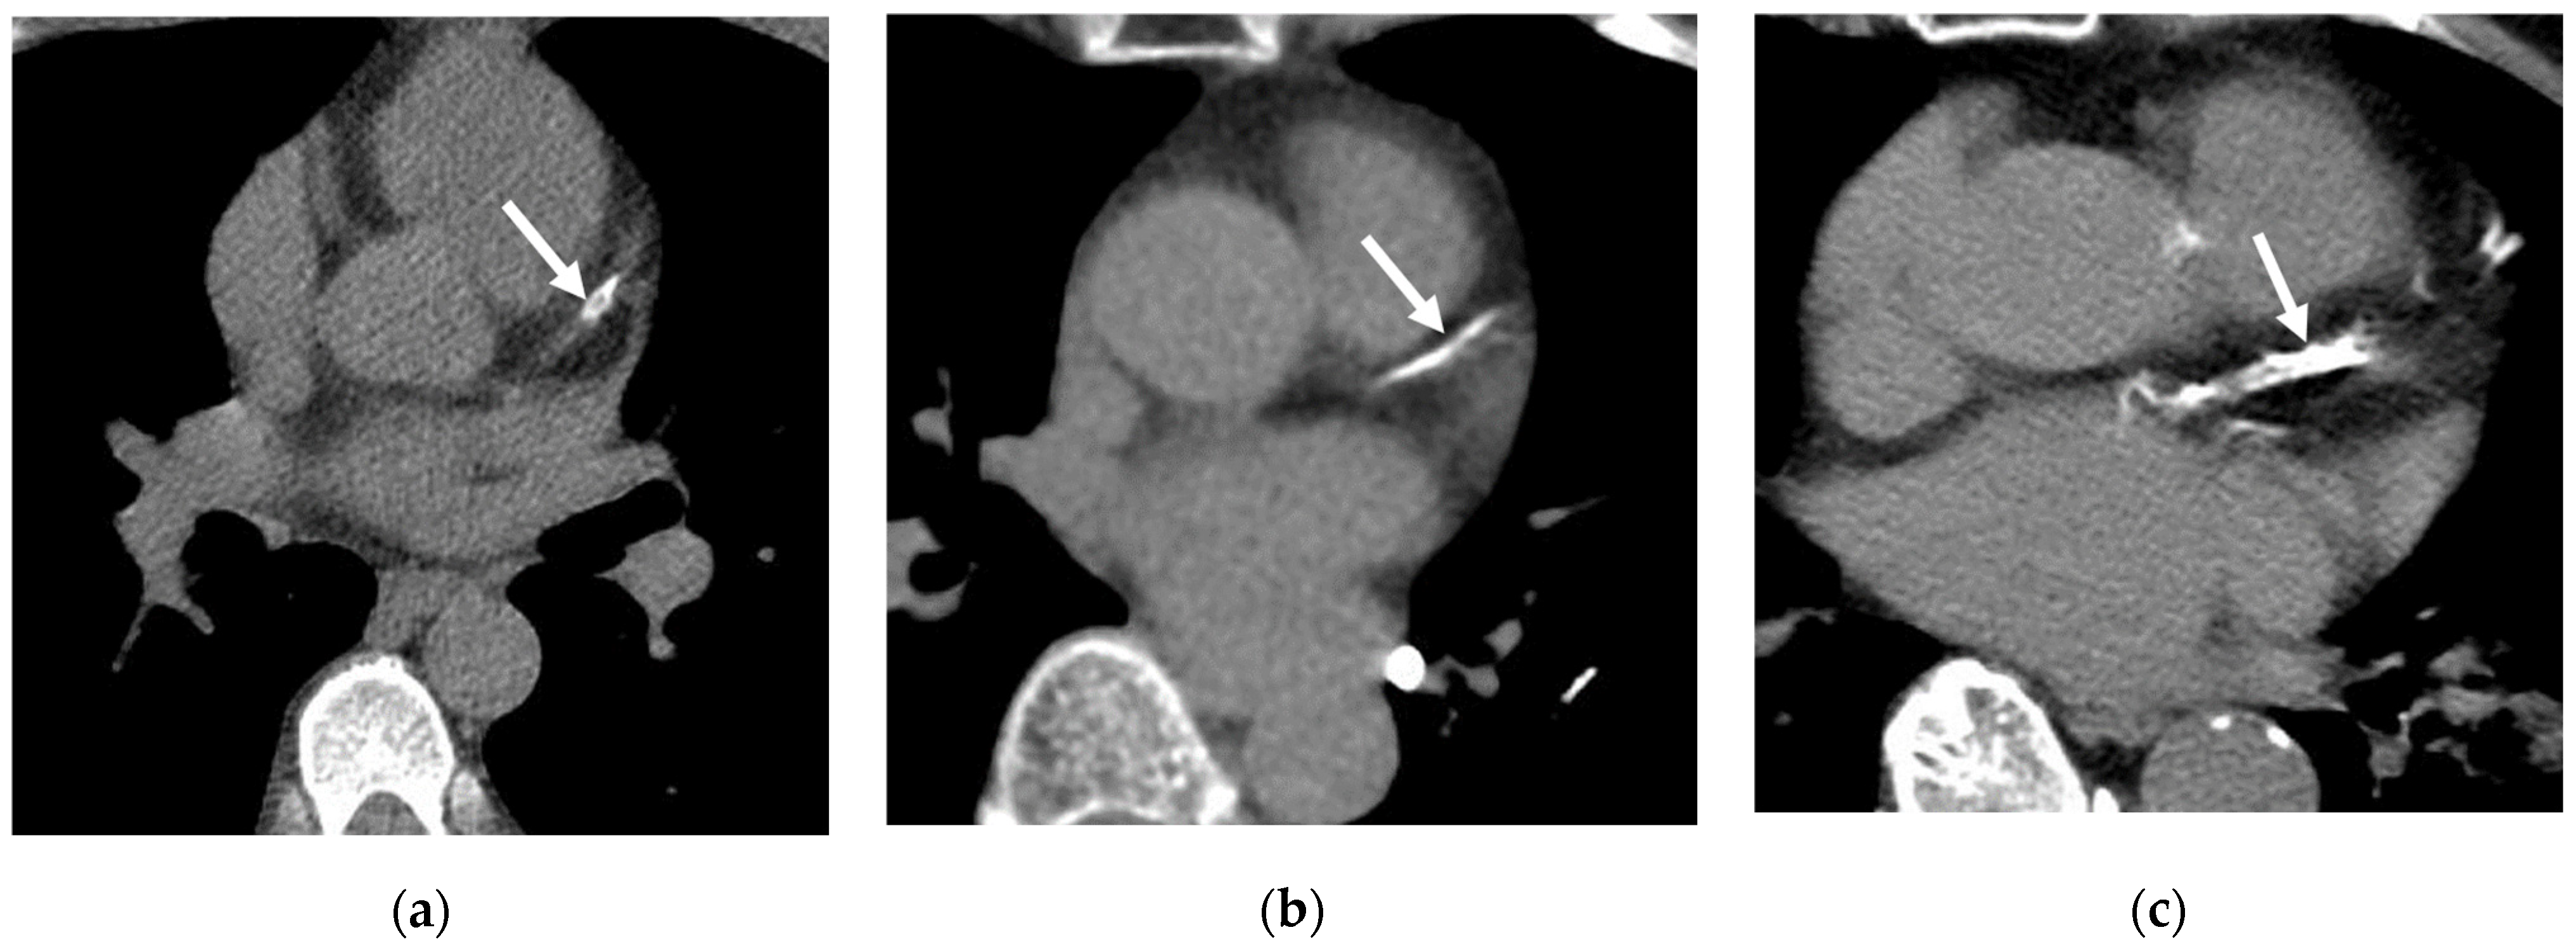

4.3. Aortic Valve Calcification (AVC)

4.1. Coronary Artery Calcifications (CAC)

4.2. Aorta and Pulmonary Artery